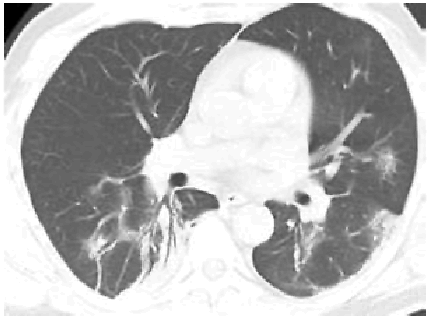

2. Наличие клинических проявлений, указанных в подпункте 1 пункта 1.3 настоящих Методических рекомендаций, в сочетании с характерными изменениями в лёгких по данным компьютерной томографии грудной клетки (далее - КТ ОГК) (приложение 1 к настоящим Методическим рекомендациям) вне зависимости от результатов однократного лабораторного исследования на наличие РНК SARS-CoV-2 и эпидемиологического анамнеза.

- Изменения в лёгких при КТ, типичные для вирусного поражения (объём поражения минимальный или средний; КТ 1-2),

- Изменения в лёгких при КТ, типичные для вирусного поражения (объём поражения значительный или субтотальный; КТ 3-4),

- Изменения в лёгких при КТ, типичные для вирусного поражения (объём поражения значительный или субтотальный; КТ 3-4),

С практической точки зрения наиболее важно пациентам с подозрением на коронавирусную инфекцию выполнять КТ ОГК согласно приложению N 1 к настоящим Методическим рекомендациям. Изменения на КТ наблюдаются у 76% больных (изменения по типу "матового стекла" - 50%, односторонние инфильтраты - 37,2%, двухсторонние инфильтраты - 46%, интерстициальные изменения - 13,6%).